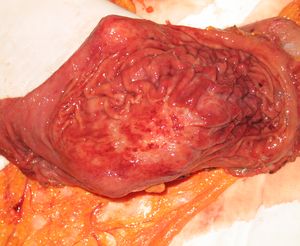

Удаленный желудок

Опухоль желудка